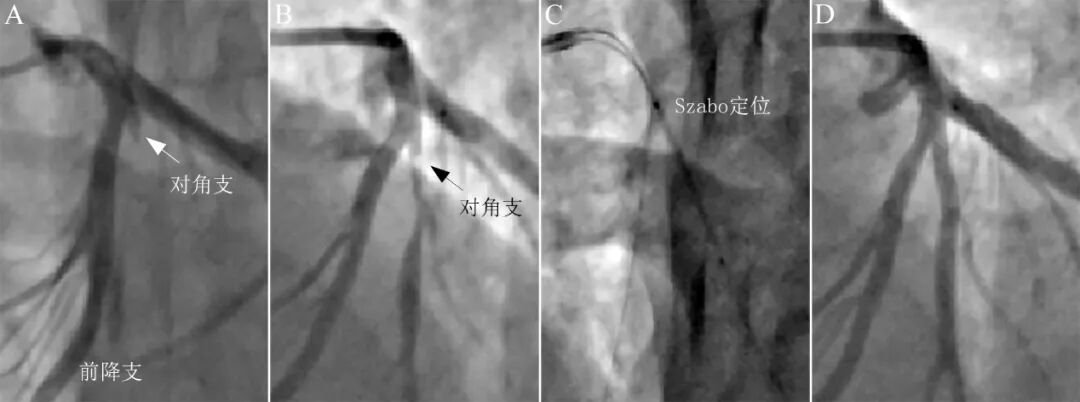

图11 Szabo精确定位处理对角支开口病变。

40岁吸烟男性,胸痛1天,心电图诊断为急性高侧壁心肌梗死。造影显示前降支近中段狭窄40%,第一对角支开口完全闭塞(A)。Sion导丝顺利通过,预扩张后提示对角支粗大,近段残余狭窄90%,开口部1-2mm基本正常,决定采用Szabo技术。齐平对角支开口植入支架(C),造影结果良好(D)。